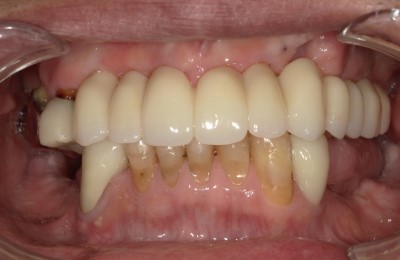

CASE01インプラント

-

Before

After

| 主訴 | 入れ歯以外の方法でしっかり咬みたい。 |

|---|---|

| 治療方法 | インプラントを6本埋入し、その上部をセラミックで作りしっかり咬めるようにした。 |

| 治療期間 | 約5カ月 |

| リスク | メンテナンスをしないことによるインプラント周囲炎、上部セラミックの破折。 |

| 費用 | 3,476,000円(税込) |